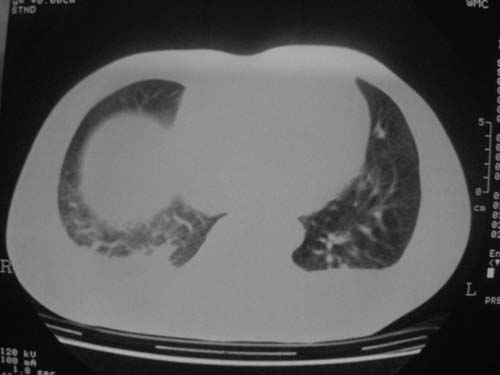

这是第五天拍的ct,纵隔窗我没都传,实在是太费时,请教各位老师,此病人有肺水肿吗?帮忙分析一下

1)双侧创伤性湿肺。2)双侧胸腔积液。

结果:病人刚入院水电解质紊乱,治疗期间大量输液,而且速度较快,正如4.5楼那样说的引起肺水肿,对症治疗后病情好转,